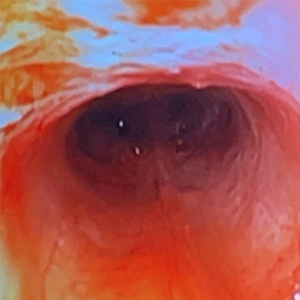

内視鏡(細い胃カメラ)で気管と喉を直接覗く検査を行いました。

気管の内視鏡検査

気管虚脱に加え、スワブ検査で炎症が見られました。

培養と細胞診の結果によるお薬の使用で、現在は比較的良好にコントロール出来ています。